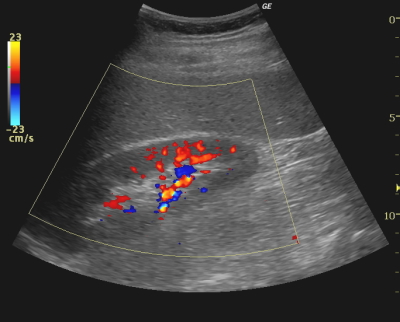

カラードプラ法(CDI:color doppler imaging)は、生体内血行動態に色を付けBモード画像上に重ね合わせながらリアルタイムで表示する方法である。

パルスドプラや連続波ドプラが、ごく狭い範囲の血流情報を定量的に表示するのに対し、カラードプラ法では2次元断層面上の広範囲に渡る血流情報が得られる。また、血流情報を波形ではなく色として表示するため視覚的に捕らえやすいという利点がある。カラー表示には速度表示の他、速度-分散表示もあり、検査対象領域により様々な表示が可能である。

カラー表示はROIを拡大するとFR等に悪影響が出る他、低速流や入射角によっては感度低下を起こす、エイリアシングは不可避といった弱点もあるため装置の調整が必要となることも多い。また実際の検査においては検査対象領域により大きく設定が変わるためプリセットをいくつか組んでおくことも大切である。